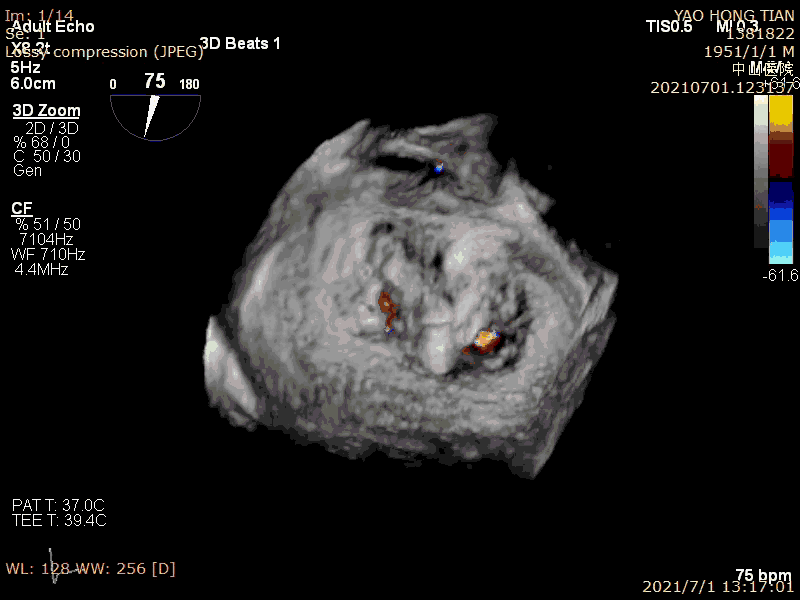

患者,男,70岁。术前超声诊断:左心室射血分数 LVEF 58%,左心室舒张末内径LVDD 52mm,左心房内径LAD 57mm,PASP 63mmHg,二尖瓣瓣尖错位导致重度二尖瓣反流,VC 6*13mm,反流面积19.8cm²(图1-2)。

术前大量反流(VC 6*13mm)

瓣尖错位导致A2P2大量反流